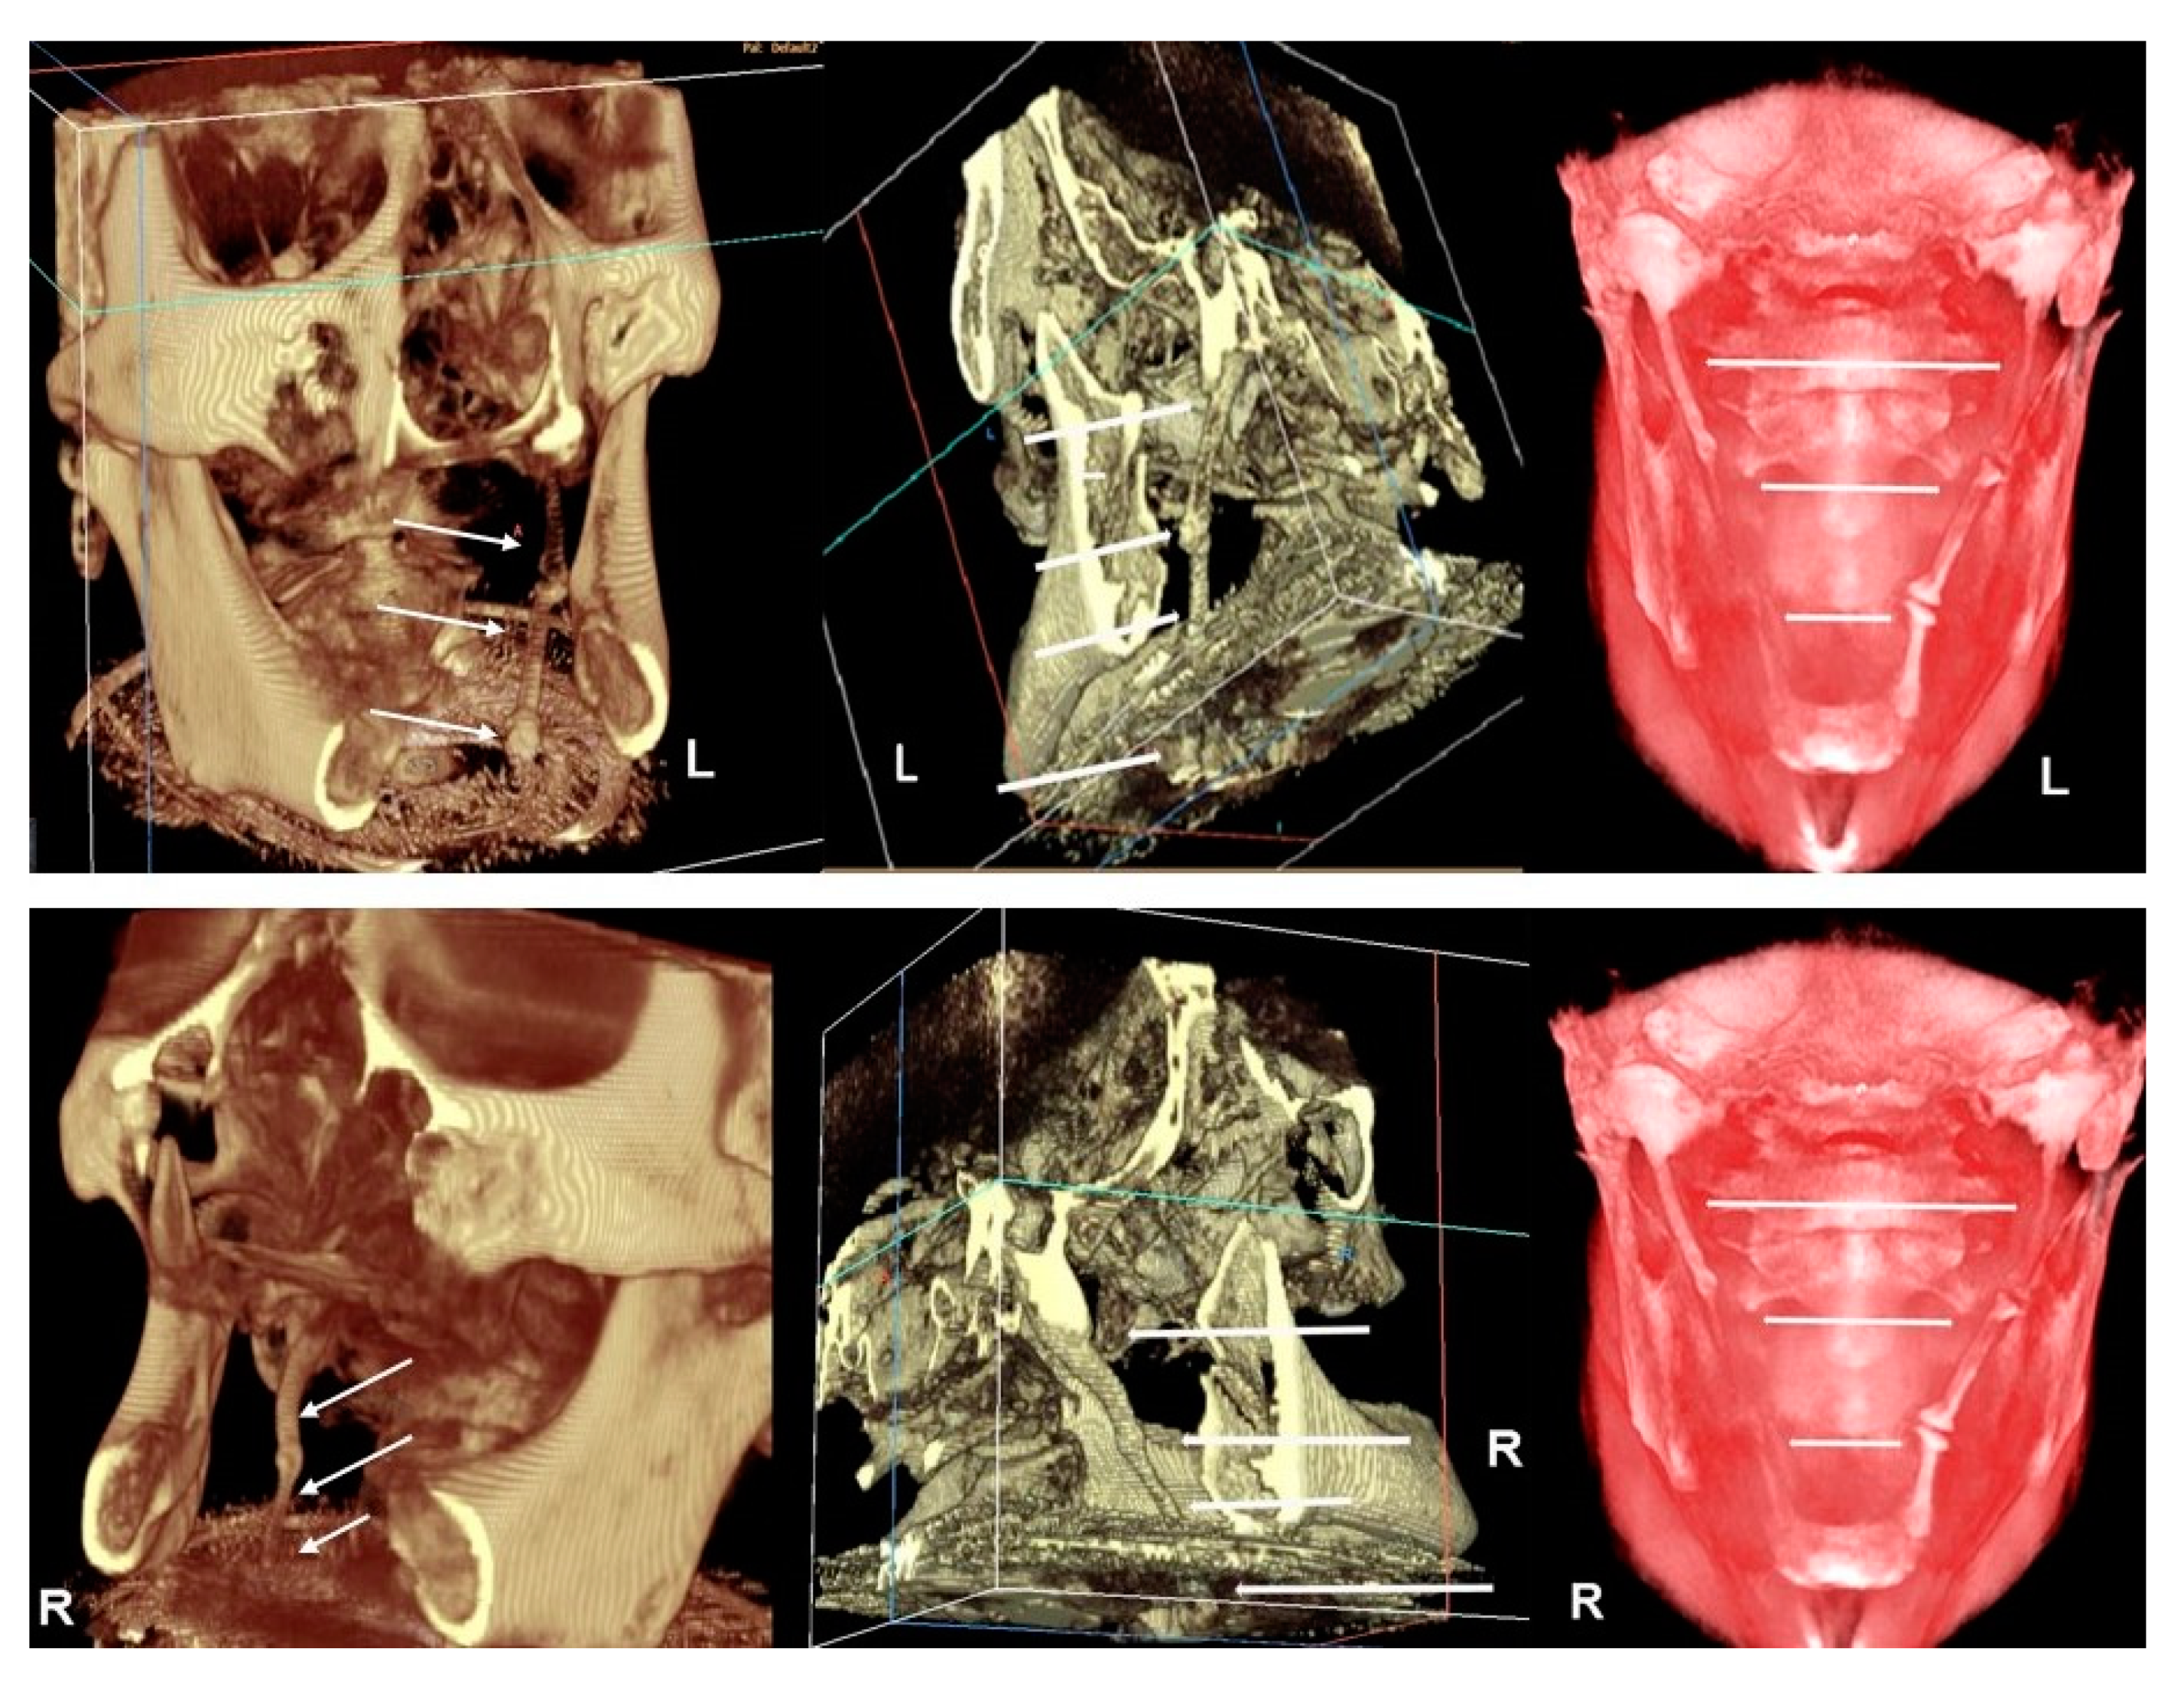

Apart from these findings, there were multiple astonishing CBCT images of the different planes, which show an impressive bilateral mineralization of the styloid complex. All the taken CBCT radiographic images showed a “collar-like” multi-interrupted and segmented calcified stylohyoid complex (SHC). On the left side, the segmented calcified styloid ligaments fully stretched to the lesser cornu of the hyoid bone and on sagittal CBCT images, measuring 85.87 mm in length with an average width of 3.63 mm, while the right side barely reached the lesser horns of the hyoid bone, measuring 81.13 mm in length with an average width of 2.58 mm (Figure 5).

Due to suspicion that this patient belongs to the Eagle’s syndrome group, additional angle measurements were performed. The measurements of important angles for 3D visualization of the SHC showed: right 53.54° (short) and left 66.8° (~normal) for the mediolateral angle (MLA), right 80.63° and left 78.78° (elongated) for the anteroposterior angle (APA), indicating wide both angles [9]. Measurements of maximum thickness with values of 4.56 mm and 3.6 mm (normal) for the right and left sides were seen, respectively. On both sides, the pattern of calcification/mineralization was almost identical, involving the tympanohyal, stylohyal, ceratohyal and hypohyal parts of the SHC (Figure 6).

Figure 5. Top image–CBCT three-dimensional reconstruction shows an impressive calcification of the SHC in different image modes (left–default 2 mode, center–default mode, right-skin/red mode throughout antero-posterior slice sectioning). On the left side, the CBCT radiographic appearance of a “collar-like” and elongated SHC shows a multi-interrupted and segmented calcified SHC, fully stretched to the lesser cornu of the hyoid bone (see arrows). Bottom image–in a different image mode, on the right side, CBCT three-dimensional reconstruction shows the segmented calcified SHC which barely reaches the lesser cornu of the hyoid bone (left–default 2 mode, center–default mode, right–skin/red mode throughout antero-posterior slice sectioning) (see arrows).